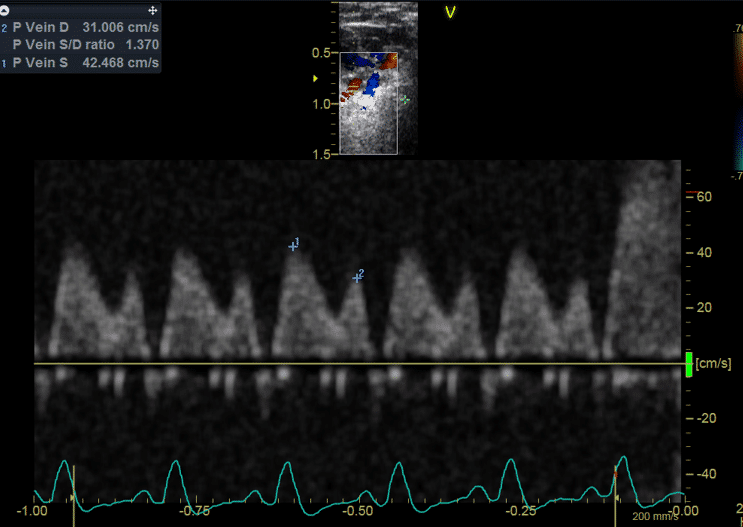

• fonction ventriculaire diastolique;

• évaluation des valves cardiaques;